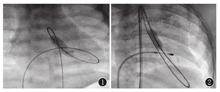

前向途径:复合麻醉后,消毒铺巾,穿刺股静脉,置入5F动脉鞘管,穿刺桡动脉监测动脉血压,通过股静脉肝素化。4F右冠状动脉造影导管(JR3.5)在0.032 inch×260 cm超滑导丝引导下,经右心房-卵圆孔-左心房进入左心室,超滑导丝经左心室-主动脉瓣-升主动脉-降主动脉,并测左心室及升主动脉压力计算跨瓣压差。交换4F猪尾导管于左心室,在正侧位投照体位下,手推造影剂行左心室造影,显示瓣口的位置及瓣环径,根据瓣环径选择合适的球囊。在超滑导丝引导下,交换4F右冠状动脉冠脉导管经左心室-主动脉瓣置于升主动脉。交换0.018 inch×300 cm亲水涂层导丝,将导丝送入降主动脉。使用美敦力冠状动脉扩张球囊导管在0.018 inch×300 cm亲水层导丝引导下置于主动脉瓣,调节球囊中央位于主动脉瓣口,用压力泵压力7 bar下快速充盈球囊(图1),直至"腰凹"消失(充盈压力参照厂家标注),随着迅速抽空球囊,重复扩张主动脉瓣2~3次。重复测压及造影,拔除动脉鞘管,压迫止血。

逆行途径及右心室起搏:复合麻醉后,消毒铺巾,穿刺右侧股静动脉,分别置入适合动脉鞘管,肝素化,必要时穿刺桡动脉监测动脉血压。经股静脉置入临时起搏导线至右心室心尖,调整起搏器参数,测试起搏效果良好。用猪尾造影导管在0.035 inch×260 cm超滑导丝或普通J型导管引导下经股动脉逆行置于主动脉根部造影,观察主动脉瓣有无反流及反流程度、瓣口负性射流显示的瓣口位置并测量主动脉瓣环径。通常选用右冠状动脉导管或端侧孔导管在0.035 inch×260 cm超滑导丝辅助下通过主动脉瓣后,送入左心室,并测量跨瓣压力阶差。然后将交换超滑导丝经主动脉-主动脉瓣口-左心室(绕圈)-主动脉瓣口-升主动脉-降主动脉建立轨道或更换J形加硬交换导丝送至左心室心尖部,并沿导丝导入合适的球囊导管。调节球囊中央骑跨于主动脉瓣口,充盈球囊(图2),直至"腰凹"消失(充盈压力参照厂家标注),随即迅速抽空球囊。在球囊充盈前即刻开始以VVI模式起搏,起搏频率为160~180次/min,球囊抽空后立刻停止起搏。扩张后重复造影及测压,评估主动脉瓣开放以及主动脉瓣关闭不全的程度。术中球囊直径选择一般为瓣环直径0.9~1.0 cm,球囊长度通常新生儿与小婴儿为2~3 cm,儿童为4 cm。本研究征得患儿监护人知情同意,并通过医院医学伦理委员会批准(批准文号:2016427A)。